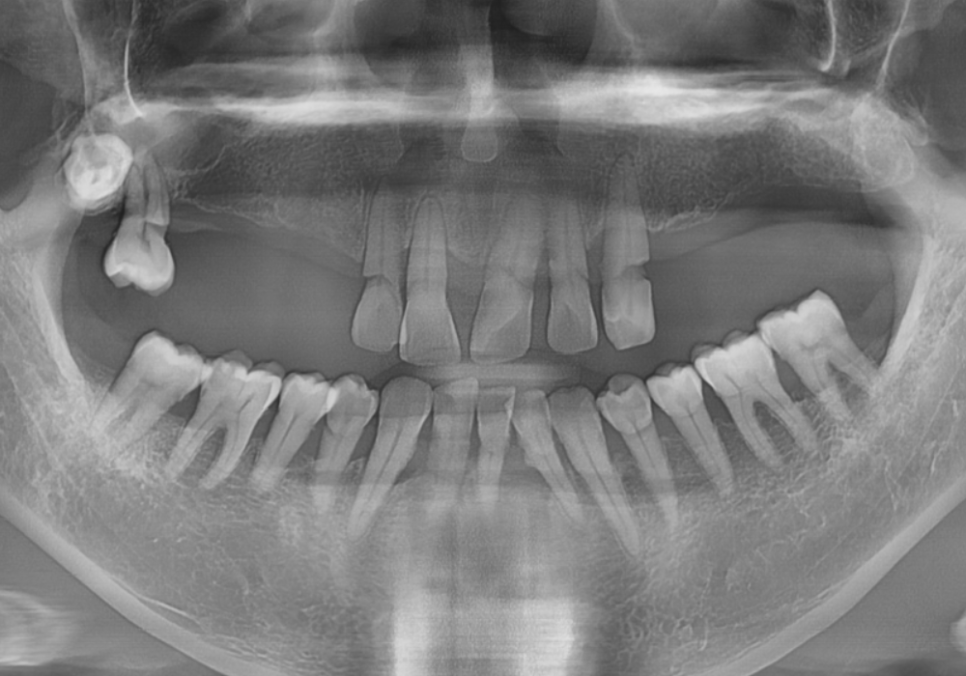

환자분의 구강 상태를 보여주는

파노라마 사진이에요.

언뜻 보셔도 치아가 몇 개 남지 않았다는 걸

금방 아실 텐데요.

위턱과 아래턱 모두 치아가 많이 빠져있고,

그나마 남아있는 치아들도 상태가 좋지 않았습니다.

치아를 잡아주는 잇몸뼈(치조골)가 많이

녹아내려 있었거든요.

특히, 틀니 고리가 걸리는 치아들에

너무 많은 힘이 쏠리다 보니,

뿌리 쪽이 심하게 패어

몹시 약해진 상태였습니다.

이렇게 되면 틀니를 아무리 새로 맞춰도

잇몸만 아프고 제대로 씹기가 참 힘듭니다.